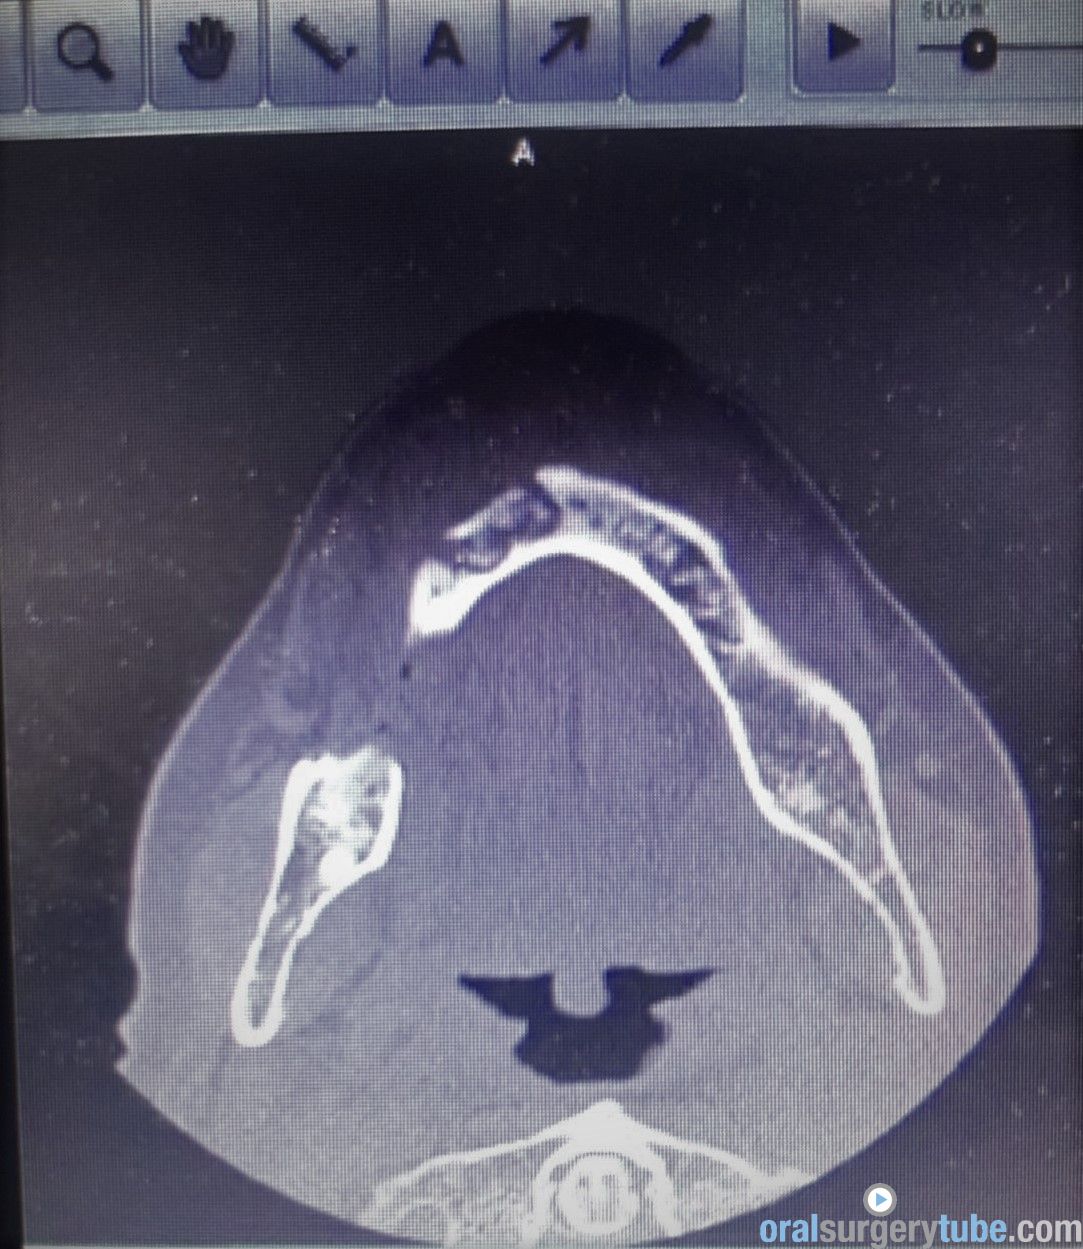

Adjuntamos también diferentes vistas del CBCT

1- ¿Quiste residual del 43? ( pero en la imagens tac,los limites no parecen muy bien definidos- ausencia de cápsula quística?)

2- ¿Fractura de la cortical vestibular con desplazamiento del fragmento y la consiguiente infeccion crónica?

3- ¿combinación de 1 + 2?